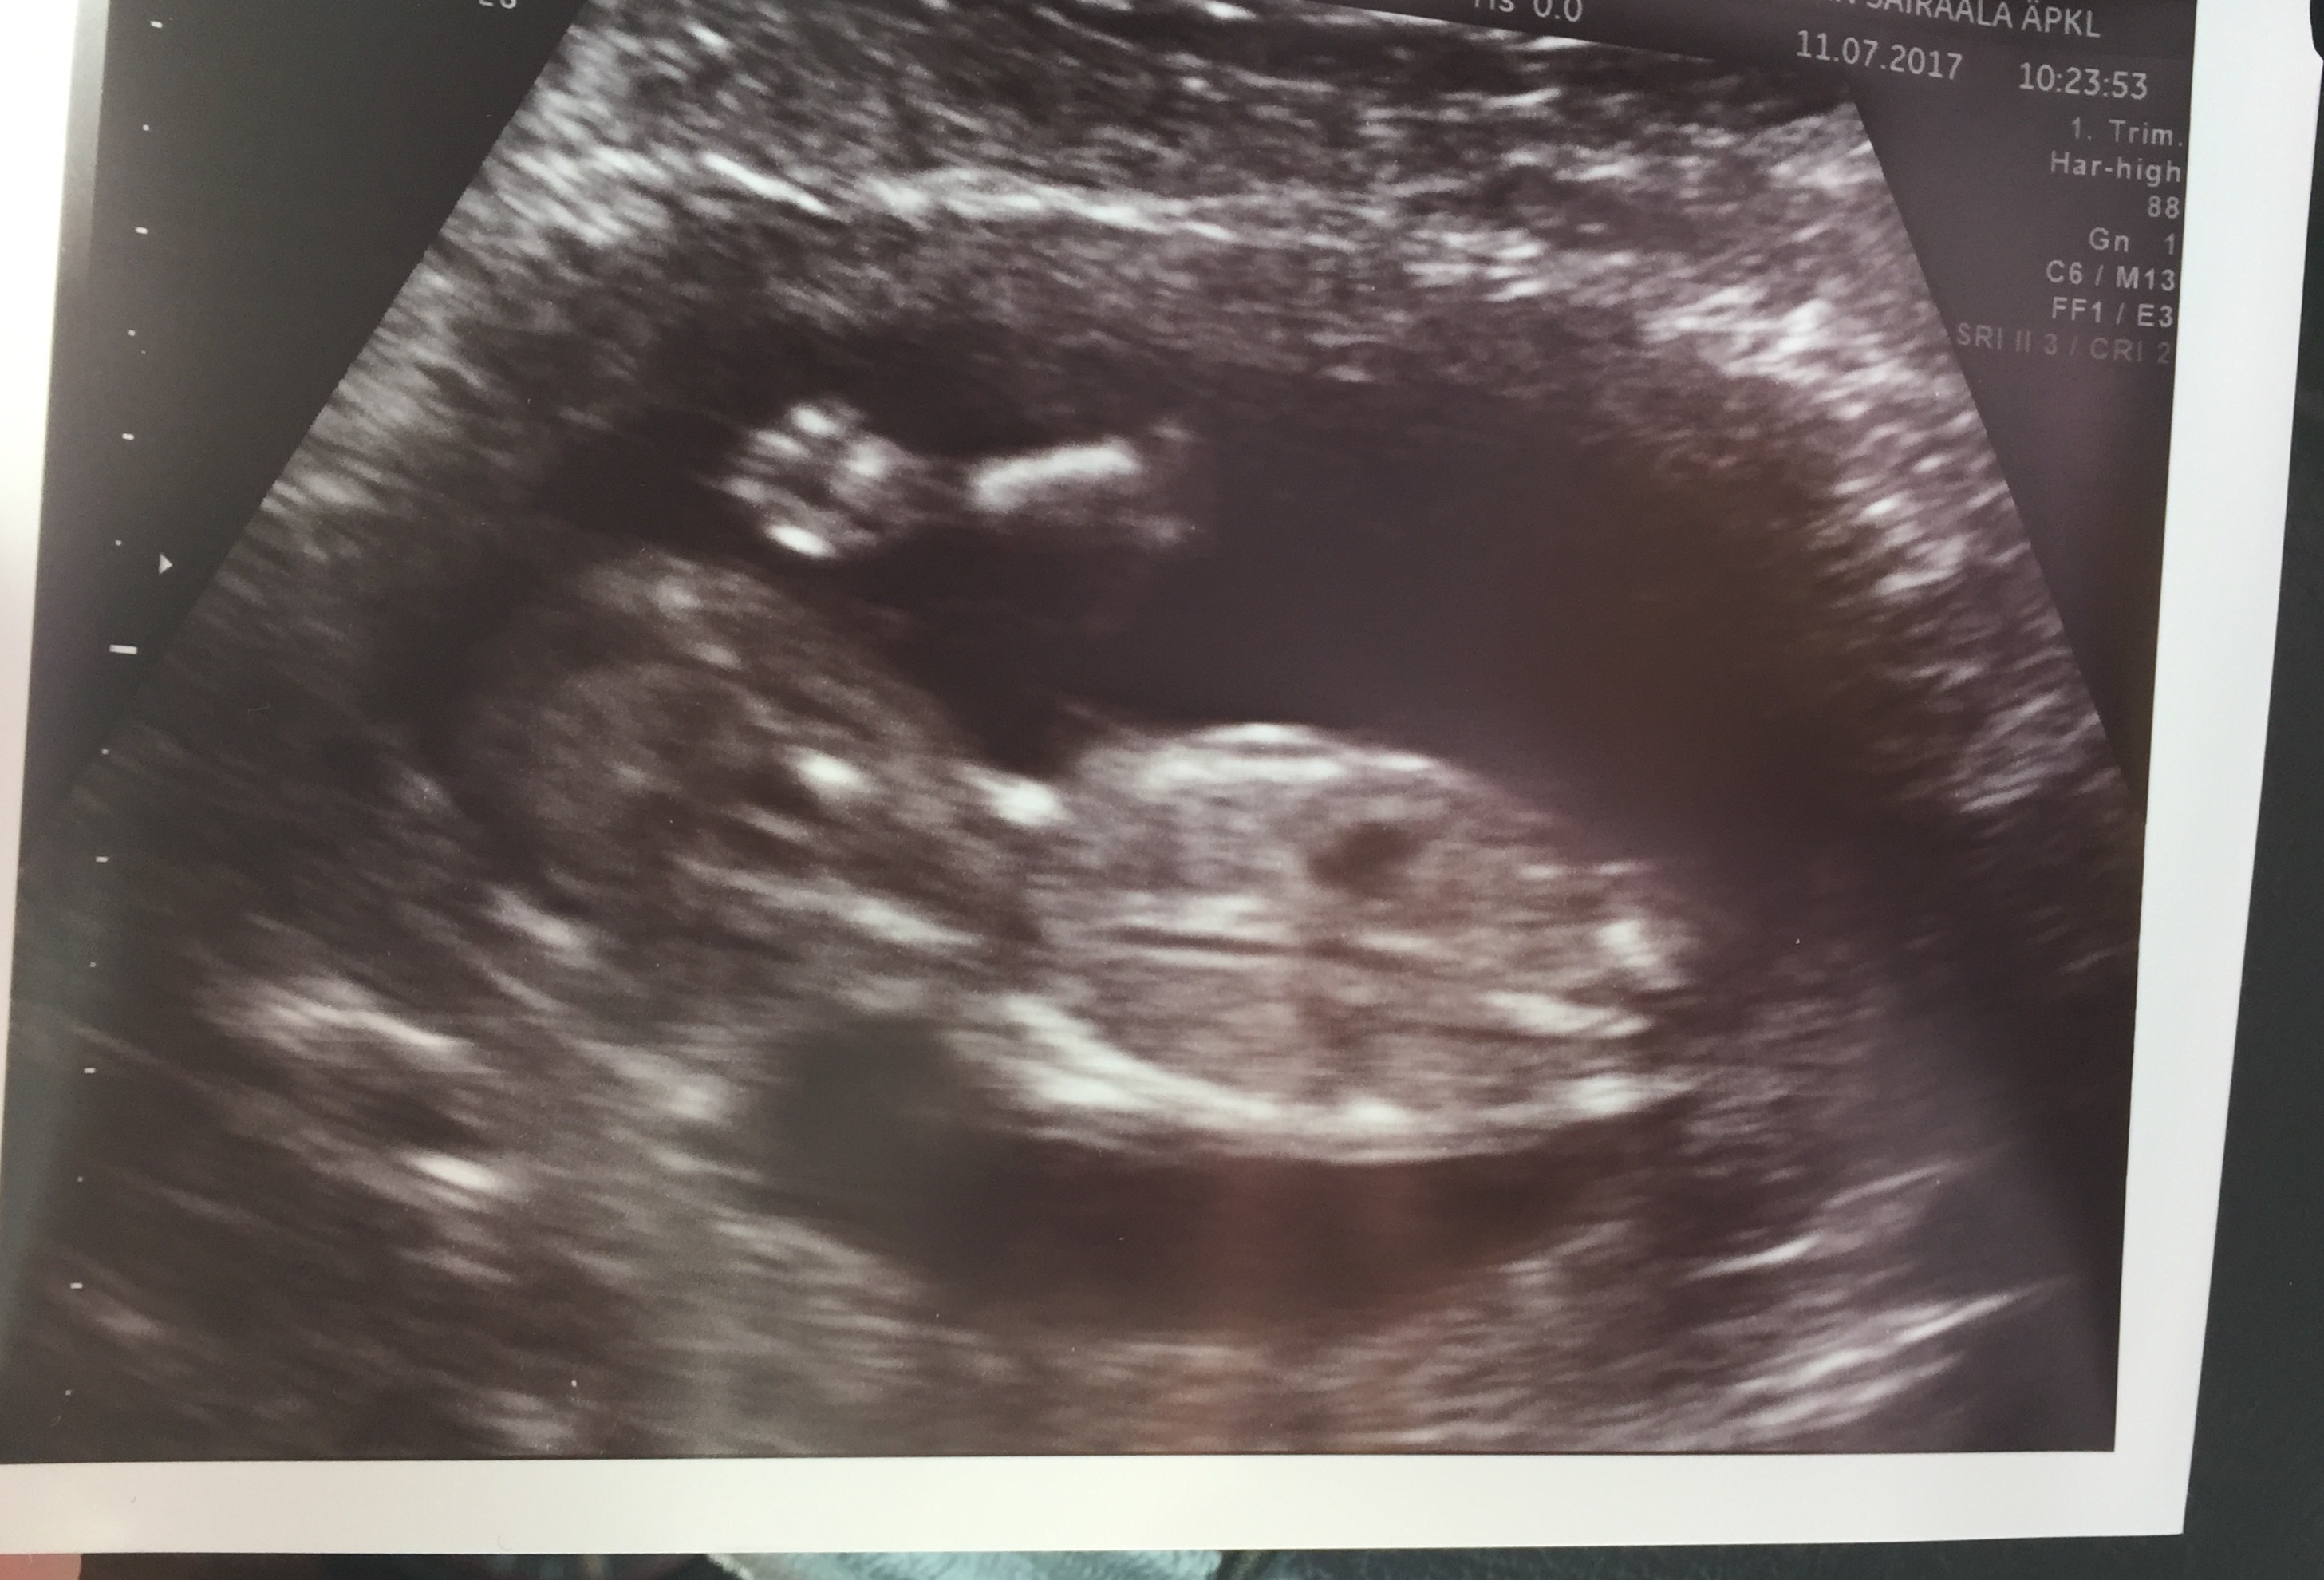

Junibealle halusin sen verran kertoa, että meillä on siis yksi 2v. poika (toiveissa olisi vielä useampi...), joka on syntynyt myös keskosena rv 30+6. Painoa oli vain 1100kg, pituutta 37cm. Mä jouduin sairaalaan jo pari viikkoa aiemmin kun oli verenpaineet pilvissä ja ultrassa selvisi että napanuorassa oli blokkeja eikä poitsu saanut tarpeeksi ravintoa. Niinpä siis raskaus piti "purkaa" ennenaikaisesti. Meillä onneks kaikki on mennyt sen jälkeen suht hyvin ja lasketun ajan tienoilla päästiin kotiin. Sairaalassa olo aika oli kyllä henkisesti rankkaa, kun olis halunnu olla koko ajan siellä mut toisaalta tuntui et päänuppi ei kestä sitä. Odotin niin et pääsee vaan kotiin pojan kanssa omiin puuhiin ilman yleisöä :) Nyt keskosuudesta on jäljellä pientä kehitysviivettä, jonka takia ollaan käyty terapioissa ja lääkäreillä. Poika kyllä hienosti kehittyy omaan tahtiinsa ja taidot löytyy ajan kanssa.